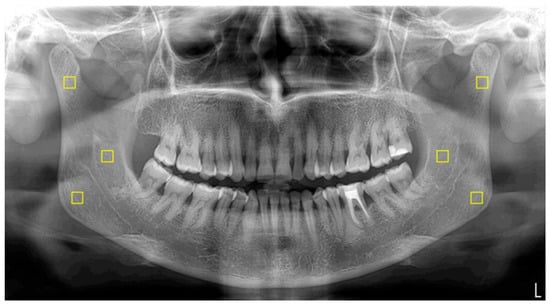

2.5. Image Processing and Fractal Analysis

The standardization of panoramic images was executed using PhotoScape X Pro 4.2.7. software (MOOII Tech, Seoul, Republic of Korea). All images were resized to 1024 × 499 pixels at a resolution of 600 dpi and saved in TIF format. FD values were determined utilizing ImageJ version 1.54 software, implementing the box-counting method introduced by White and Rudolph [18,19]. Regions of interest (ROIs) measuring 25 × 25 pixels were bilaterally selected from the mandibular angle, ramus, and condylar neck (Figure 1). Each ROI was subjected to digital preparation, including rotation, magnification, cropping, and duplication. A Gaussian blur filter was applied to reduce grayscale density variations and to emphasize trabecular structures (Figure 2). The resulting values were then plotted on a logarithmic scale to determine the slope of the line that best fit the points on the graph, which was defined as the FD (Figure 3).

Figure 1. ROIs selected from the right and left condylar, mid-ramus, and angulus bone areas in a panoramic image. The ROIs are highlighted with yellow squares.